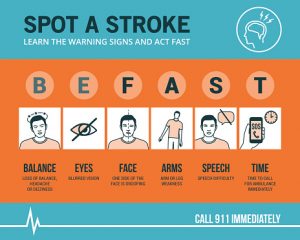

For those at risk, a stroke can occur at any moment. It occurs when a blood vessel in the brain becomes blocked, restricting oxygen-rich blood from reaching brain cells. Strokes are the third leading cause of death in the United States, with more than 140,000 people dying from the event every year. If death does not occur, severe long-term disability is often a result. While it is more common to suffer from a stroke in the later years of our lives, it can happen at any age.

For those at risk, a stroke can occur at any moment. It occurs when a blood vessel in the brain becomes blocked, restricting oxygen-rich blood from reaching brain cells. Strokes are the third leading cause of death in the United States, with more than 140,000 people dying from the event every year. If death does not occur, severe long-term disability is often a result. While it is more common to suffer from a stroke in the later years of our lives, it can happen at any age.

When the blood flow to an area of your brain is inhibited, you experience a stroke. The lack of blood causes your brain cells to starve for oxygen, ultimately resulting in their death. A massive stroke, however, is more serious and results in severe brain damage or death. By massive we mean that a huge area of the brain was affected and a lot of damage was done.

Understanding the differences between a stroke and a heart attack can help you get the appropriate help. They are both medical emergencies and can alter a person’s life, yet a stroke and heart attack are not exactly the same.

While they may be related, there is a difference between a stroke and a heart attack. Sadly, about every 43 seconds, someone in the United States suffers a heart attack. Approximately 800,000 Americans experience a stroke every year. So, how do we explain what distinguishes a stroke from a heart attack? Well, a heart attack happens when blood flow to part of the heart becomes blocked. Without oxygenated blood, heart muscles start to die. However, in the case of a stroke, the brain is impacted. The brain attack occurs when blood flow and oxygen to the brain is cut off. This can take place if a blood vessel that feeds the brain gets clogged or bursts. Continue reading…